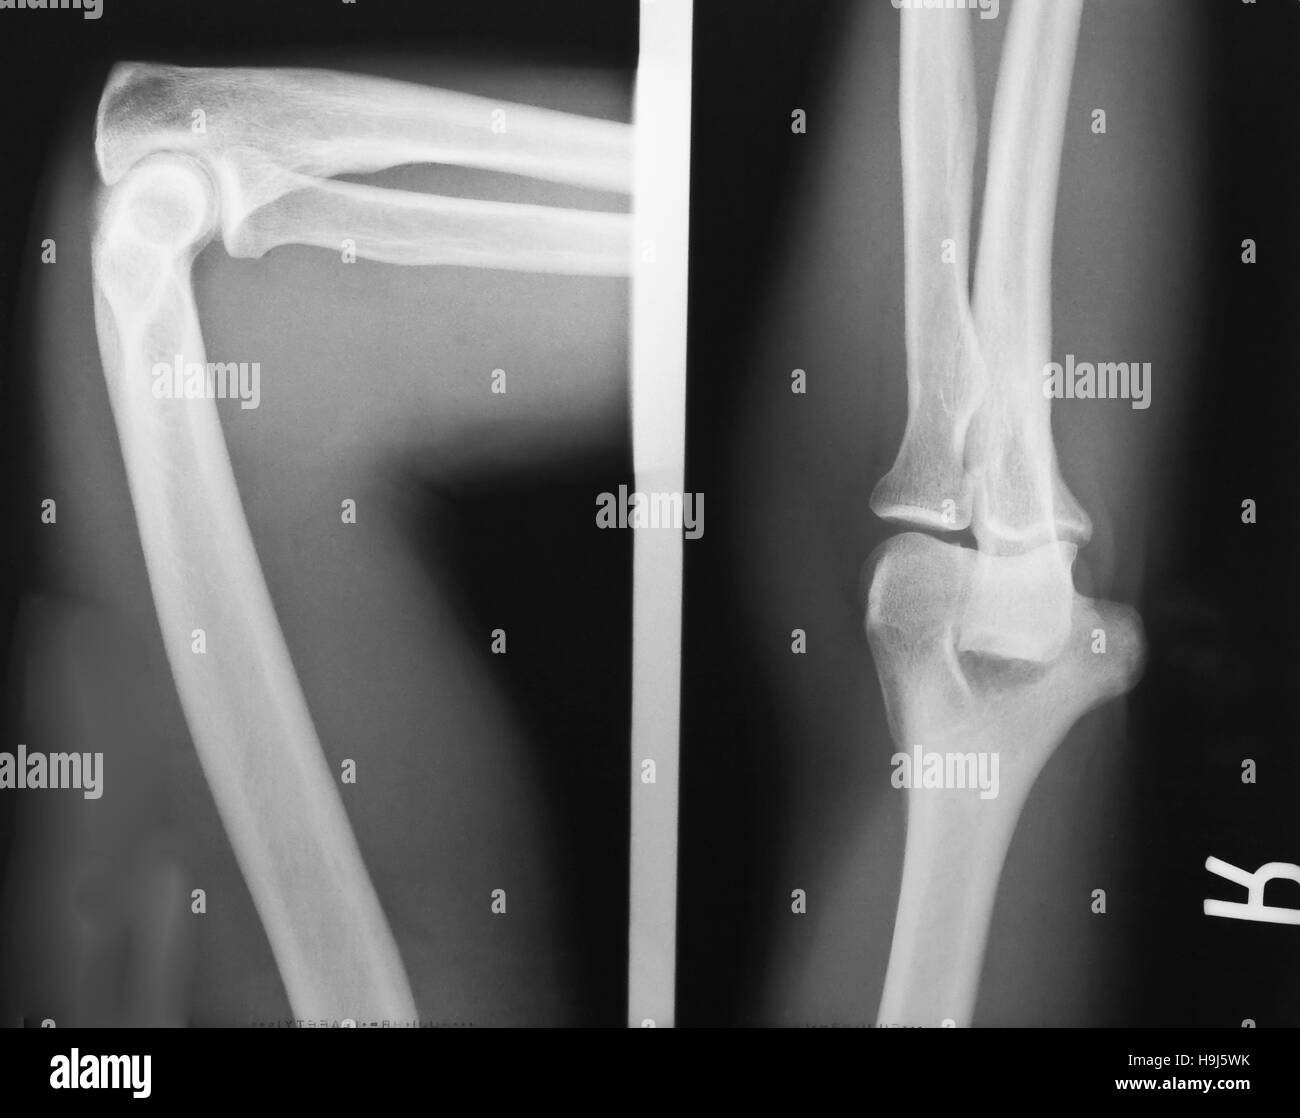

X Ray Of The Elbow Joint .   the elbow is a complex synovial joint formed by the articulations of the humerus, the radius, and the ulna.   optimal elbow radiographic technique requires the patient to tolerate, and cooperate with, full extension of the elbow for. Suspected fracture of the proximal radius and ulna. The elbow is the joint connecting the upper arm to the forearm. Last updated november 2, 2023 • 44 revisions •.   written by oliver jones.  the radius (forearm bone on the thumb side) the surfaces of the bones where they meet to form the elbow joint are covered with articular cartilage, a.